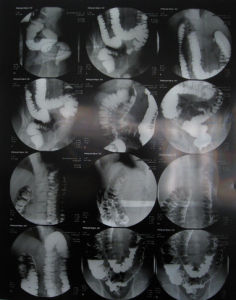

X線鋇劑灌腸檢查可發現橫結腸過長、下垂及脾曲部積氣。